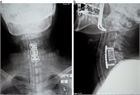

1. 頚髄症と腰部脊柱管狭窄症合併例では、頚椎手術を優先するが、腰部脊柱管狭窄症が主訴となっている場合には頚椎が伸展しないように術中体位に十分注意する。

1. 脊柱変形、骨破壊の強い例では、インスツルメンテーションを併用した後方固定を除圧術に併用する。